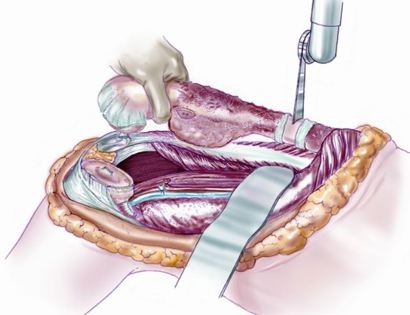

Blood Vessel and Nerve Dissection

Separating all major arteries, veins, and nerves from the tumor. In rare cases a nerve (s) may need to be removed if it is involved by the bone sarcoma. For this procedure it is vital that the femoral vessels (femur artery and veins), popliteal vessels (arteries and veins around your knee joint), and sciatic nerve are properly identified. Once the blood vessels and nerves are properly identified they can be retracted (moved away) and protected throughout the procedure.

Soft Tissue Coverage

Soft tissue coverage of the prosthesis. Multiple muscle rotation flaps are used to restore function and stability of the knee as best as possible. The goal is to provide a stable knee so the extremity can function well. Soft-tissue reconstruction that involves rotating and reattaching the surrounding muscles, including the gastrocnemius (calf muscle) and vastus medialis (quadriceps muscle). Restoring the function of the surrounding muscles and knee joint is most important for achieving optimal functional outcomes and for protecting the prosthesis from infection.